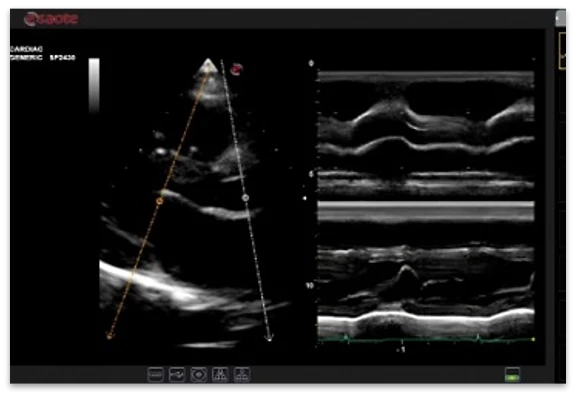

B rejimi

M rejimi

Anatomik M-rejimi (CMM)

Yurak-qon tomir tadqiqotlari uchun kardio to'plami